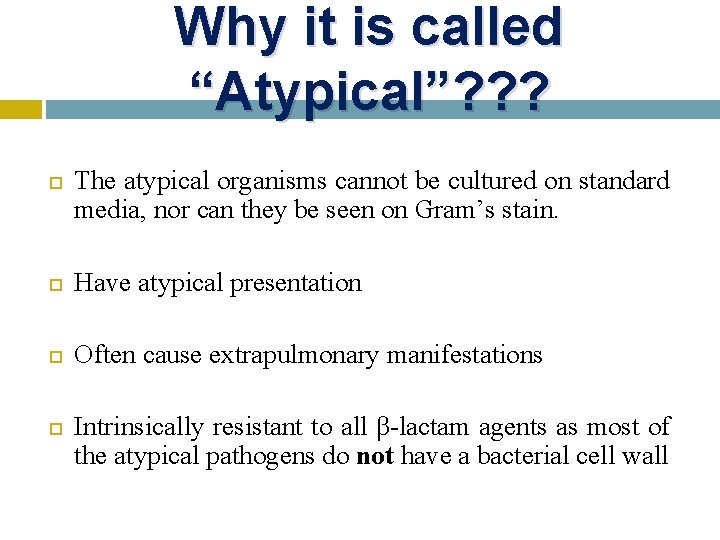

Why it is called “Atypical”? ? ? The atypical organisms cannot be cultured on standard media, nor can they be seen on Gram’s stain. Have atypical presentation Often cause extrapulmonary manifestations Intrinsically resistant to all β-lactam agents as most of the atypical pathogens do not have a bacterial cell wall